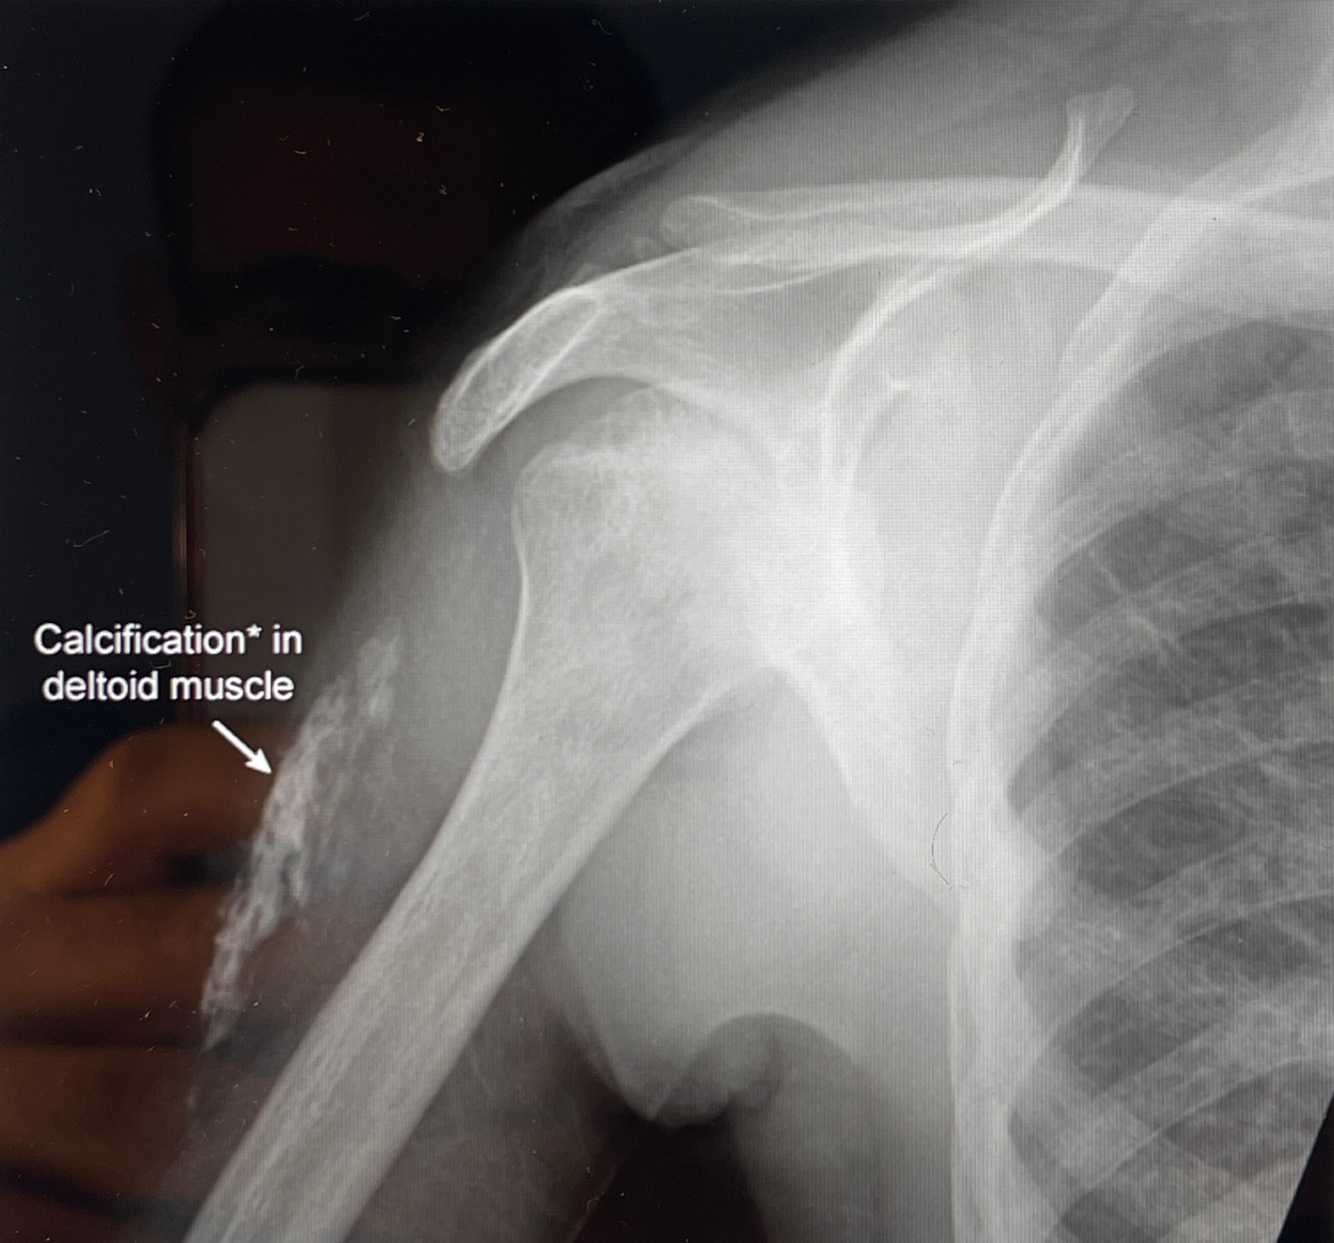

A

How well did you know this?